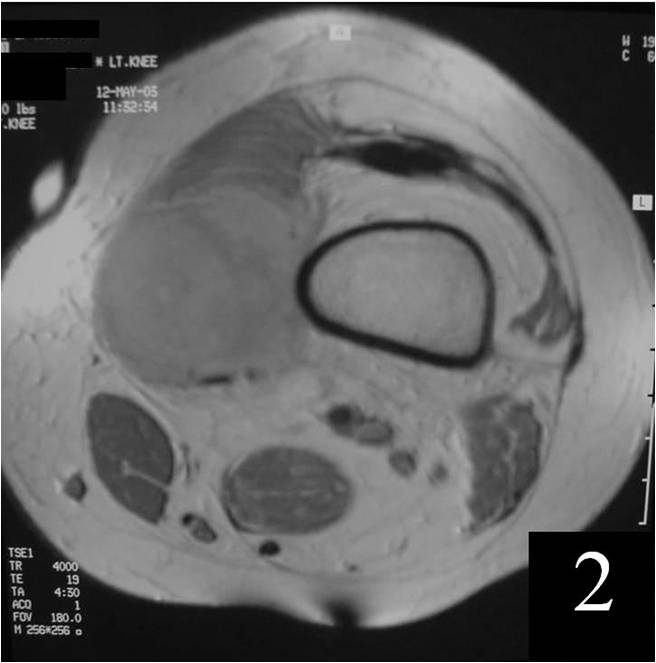

MRI

Nonspecific nonfatty mass (Fig. 2,3)

Isointense to skeletal muscle on T1W

Usually heterogeneous on T2W SE